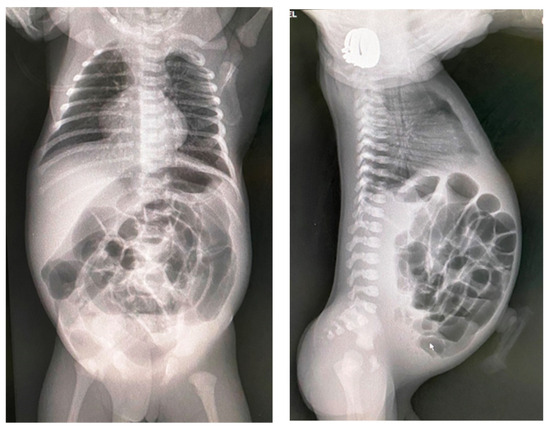

3.2.1. Simple Meconium Ileus

3.2.2. Complicated Meconium Ileus